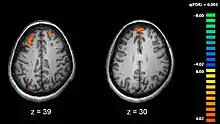

The areas most actively involved in episodic encoding and retrieval are the medial temporal lobe (hippocampus) and the prefrontal lobe.

Recent research using neuro-imaging technology including PET and fMRI scanning has shown that there is an extensive amount of distributed brain activation during the process of episodic encoding and retrieval. Among the various regions, the two most active areas during the constructive processes are the medial temporal lobe (including the hippocampus) and the prefrontal cortex.[15] The Medial Temporal lobe is especially vital for encoding novel events in episodic networks, with the Hippocampus acting as one of the central locations that acts to both combine and later separate the various features of an event.[16][17] Most popular research holds that the Hippocampus becomes less important in long term memory functioning after more extensive consolidation of the distinct features present at the time of episode encoding has occurred. In this way long term episodic functioning moves away from the CA3 region of the Hippocampal formation into the neocortex, effectively freeing up the CA3 area for more initial processing.[17] Studies have also consistently linked the activity of the Prefrontal Cortex, especially that which occurs in the right hemisphere, to the process of retrieval.[18] The Prefrontal cortex appears to be utilized for executive functioning primarily for directing the focus of attention during retrieval processing, as well as for setting the appropriate criterion required to find the desired target memory.[15]